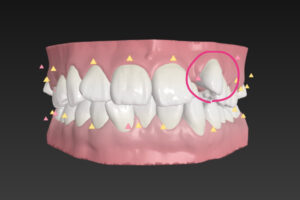

正面

歯並びガタガタの

そうせい を気にして

今回の治療ポイント①

うえ 2 問題

そくせっし は真ん中から数えて2番目

この歯は内側に入り込んでいて

とても動きにくいので

右上の だいに だいきゅうし は

下の歯の外側に出ていて

名前は はざみ状こうごう

英語ではシザーズバイト

この歯並びは下の歯と咬んでないので

食べ物を すりつぶすのが無理

シザーズバイト